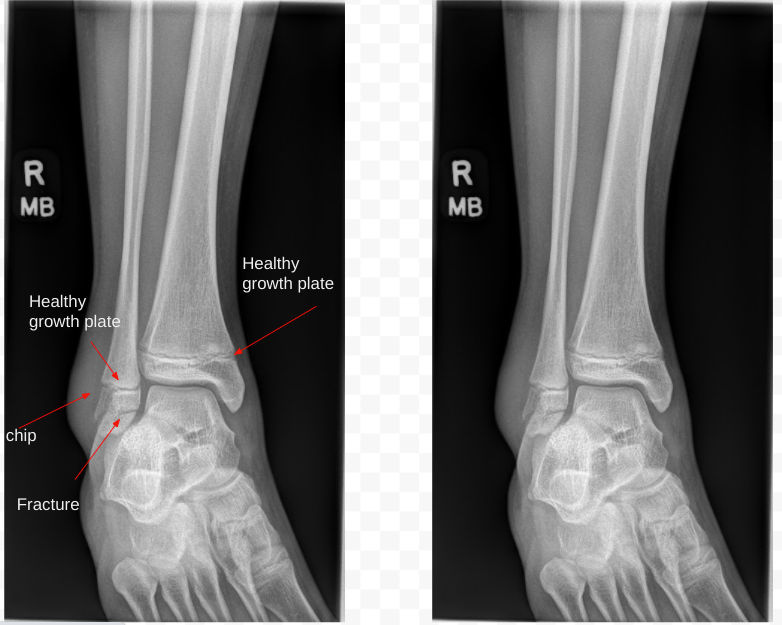

My gymnast, who has never sustained an injury, broke her fibula at the ankle height. Our first week after the fracture involved 2 splints and 3 casts. When she received her first cast, she chose blue and had her friends all sign it. The second cast could only be black and she used silver to decorate it with stars and new signatures. The third cast could also only be black and at this point she decided to just leave it black. The many reasons for different splints/casts were swelling, numbness relief, first cast, better cast placement, then needed to replace a cast due to shower cover (garbage bag/elastic) fail.